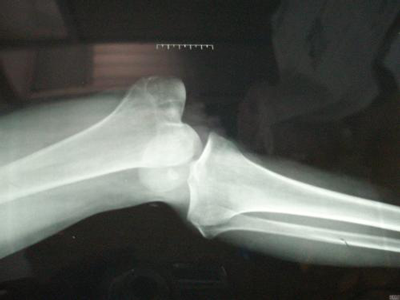

凡关节遭受外力作用,使构成关节的骨端关节面脱离正常位置,引起功能障碍者,称为外伤性脱位(简称脱位)。

脱位是指机体关节遭受外力作用,使构成关节的骨端关节面脱离正常位置,引起功能障碍。